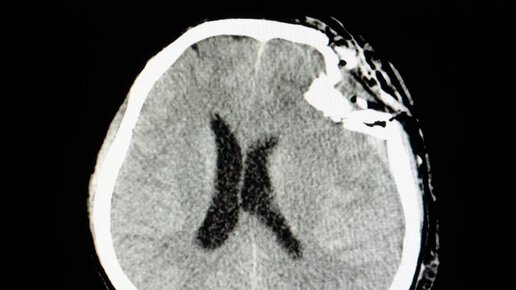

Отек головного мозга - характеристика.

Мозг - это основной орган центральной нервной системы, благодаря которому мы можем получать, обрабатывать и генерировать раздражители. Таким образом, очевидно, что каждое его нарушение представляет собой огромную угрозу для здоровья и жизни человека...